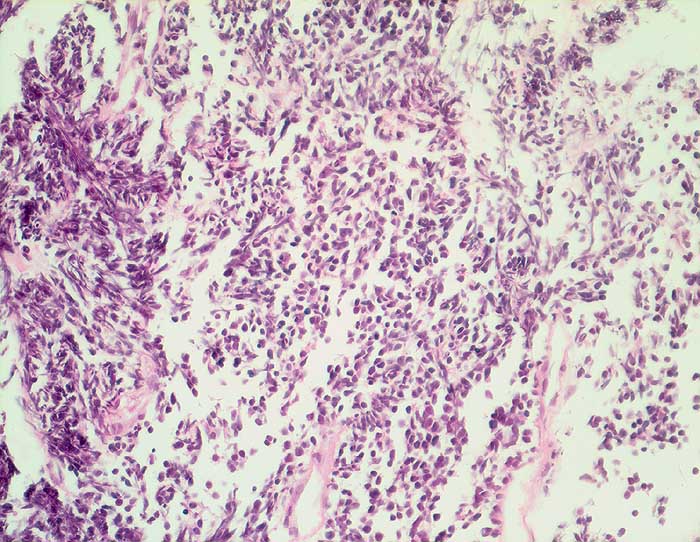

Kleinzelliges Bronchuskarzinom

Der Nachweis des kleinzelligen Karzinoms gelingt im Sputum meist leichter als im Bronchialsekret. Im Bronchialsekret sind die Tumorzellen oft zwischen Flimmerzellen und Entzündungszellen versteckt, während die stark hyperchromatischen Kerne im Sputum schon bei schwacher Vergrösserung ins Auge fallen. Die fast nacktkernigen Zellen liegen einzeln oder bilden schmale zeilenförmige Verbände und Haufen. Innerhalb der Verbände schmiegen sich die Kerne eng aneinander (=molding). Die Kerne sind zwei- bis dreimal so gross wie Lymphozyten. Im Sputum erscheinen die Karzinomzellen kleiner als im Feinnadelpunktat, Bürstenabstrich oder Bronchialsekret.

Basalzellen sind monomorpher und bilden kleine, regelmässige kompakte Verbände. Lymphomzellen liegen stets einzeln. Feindisperse Chromatinverteilung und zeilenförmige Verbände sprechen gegen ein Lymphom. In Zweifelsfällen erfolgt die Unterscheidung immunzytochemisch (Panzytokeratin und CD45).